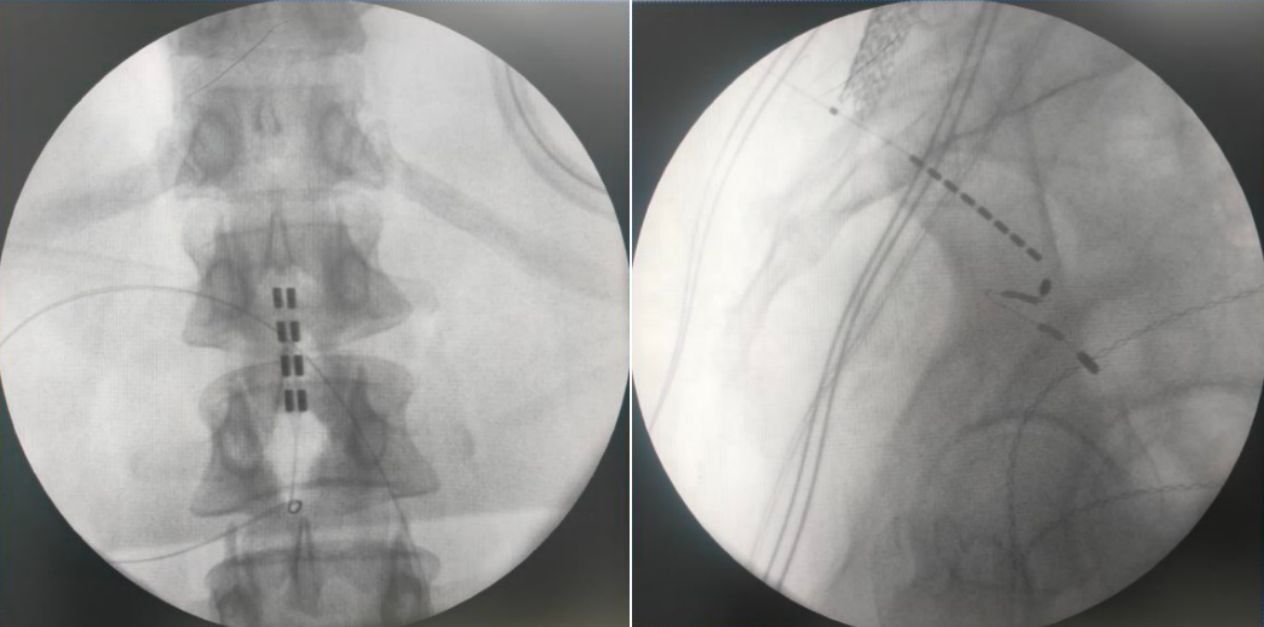

由于該患者為脊髓拴系,脊髓位置偏低,而且脊柱裂合并骶椎骨性解剖畸形給骶孔穿刺帶來了非常大的難度,但是通過術(shù)前的系統(tǒng)評估以及術(shù)中電生理監(jiān)測,李萃萃主任團(tuán)隊將一根穿刺電極精準(zhǔn)置入S3骶孔位置以改善二便功能,另一根4-4排布的片狀電極覆蓋L1-2節(jié)段(患者脊髓低位,放置位置需根據(jù)患者情況個性化調(diào)整)以調(diào)控下肢肌張力異常和感覺障礙。術(shù)中測試顯示,骶神經(jīng)刺激可有效引發(fā)二便感知,脊髓電刺激則完整覆蓋臀部及雙下肢。